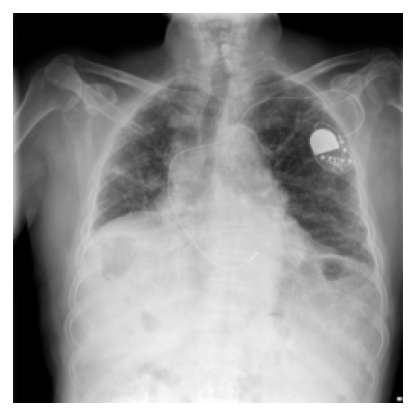

Layer-wise GradCAM: layer1 through layer4 on hiatal hernia

Layer-wise GradCAM on hiatal hernia (MoCo v2)

MoCo's layer2 encodes chest-specific structural context: rib cage geometry, lung field boundaries, and mediastinal shape, which serves as the scaffolding layers 3 and 4 build upon to localize disease. Because MoCo's layer2 is calibrated by a global contrastive loss at layer4 learning which cues pull similar whole images together, unfreezing layer2+ allows the model to reweight those structural features specifically for the target disease.